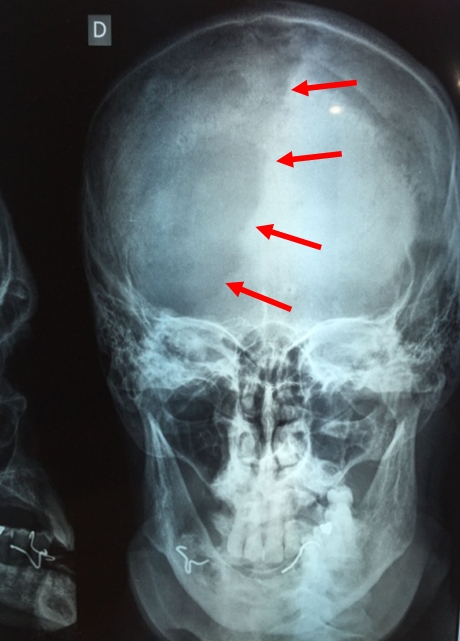

Radiografía de cráneo

Se observa imagen osteolítica en cráneo a nivel parietal izquierdo asociada a enfermedad de Paget (fase de intensa actividad resortiva osteoclástica), la cual se encuentra bien delimitada del hueso adyacente normal. A esta lesión se la denomina osteoporosis circunscripta. (Las flechas rojas marcan el límite externo de la lesión)